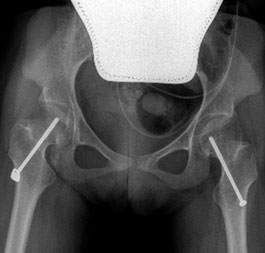

One of the surgical procedure, originally described by Professor Portinaro and his team, to maintain or restore the correct relationships between the femur and the acetabulum, is called temporary medial hemiepiphysiodesis of the proximal femur (TMH-PF). Epiphysiodesis is a surgical procedure that aims to stop or slow the growth of a cartilage.

The surgical technique consists of inserting a cannulated screw into the femoral neck to prevent the femoral head from progressively move out of its natural socket.

In all the patients, surgery allowed to perfectly reach the goal of a total containment of the hip inside the acetabular socket persistent over the years.

The advantages of this unique and never described before intervention are the possibility of performing it in outpatient procedure with an average hospitalization time of 2.30 hours. The patient feels no pain thanks to the minimally invasive–percutaneous surgery and the possibility of immediate loading.